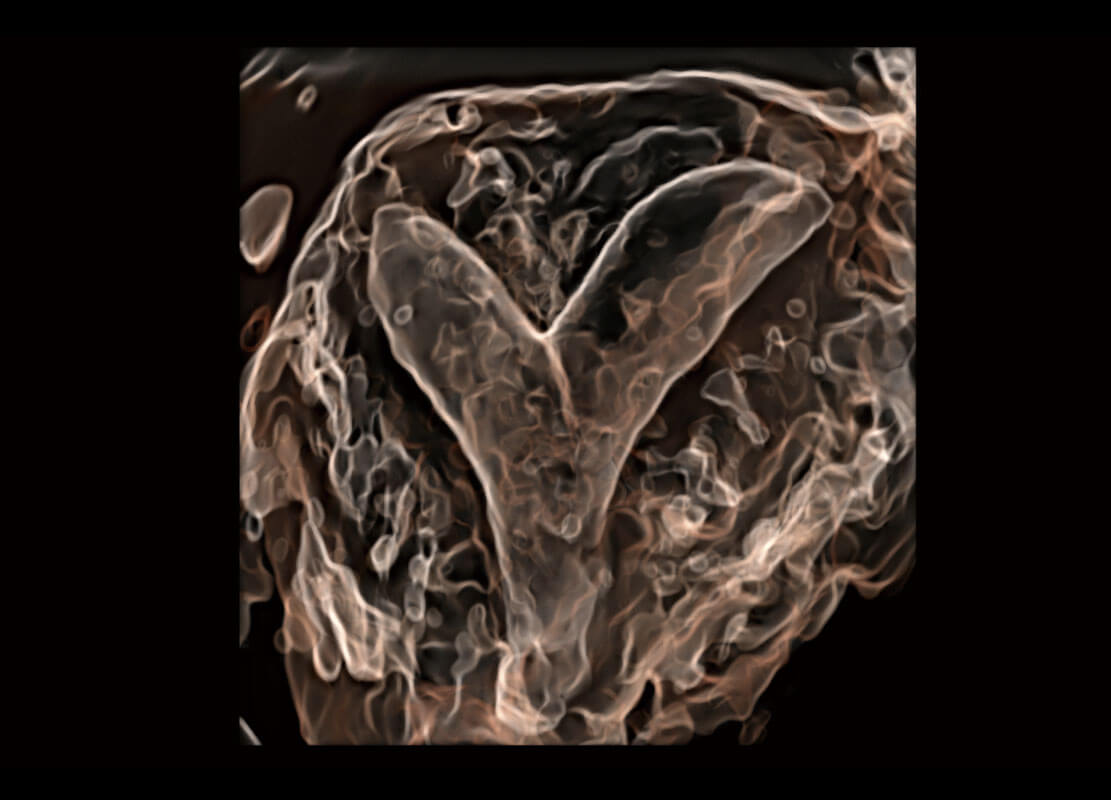

腔内三维-光影成像